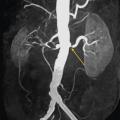

Le tableau résume les avantages et inconvénients respectifs des 3 examens de référence. L’artériographie est réservée aux revascularisations (fig. 4), et n’a pas de place à titre diagnostique.

En cas de fibrodysplasie, les lésions sont multiples, distales, souvent bilatérales, avec aspect en « collier de perles » (fig. 4). Il est recommandé, dans cette pathologie qui est souvent multifocale, de rechercher d’autres lésions artérielles (sténoses ou anévrismes) au niveau des artères digestives, cervicales et intracrâniennes.